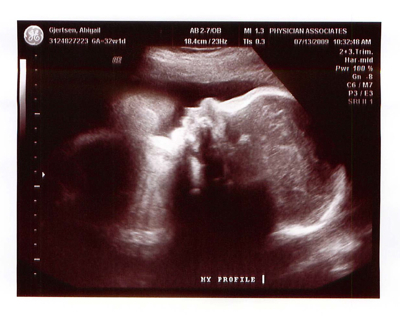

Here is the face of Valor a week and a half ago, at 32 weeks. What a chub! Look at that chin! At that appointment, he was measuring in the 64th percentile for size, estimated to be 4 lbs. 8 oz.! We couldn’t help but think of little Jamesey, who struggled so hard to get to the four-pound mark during his second month in the NICU. He hit it four or five times before he finally kept the weight on.